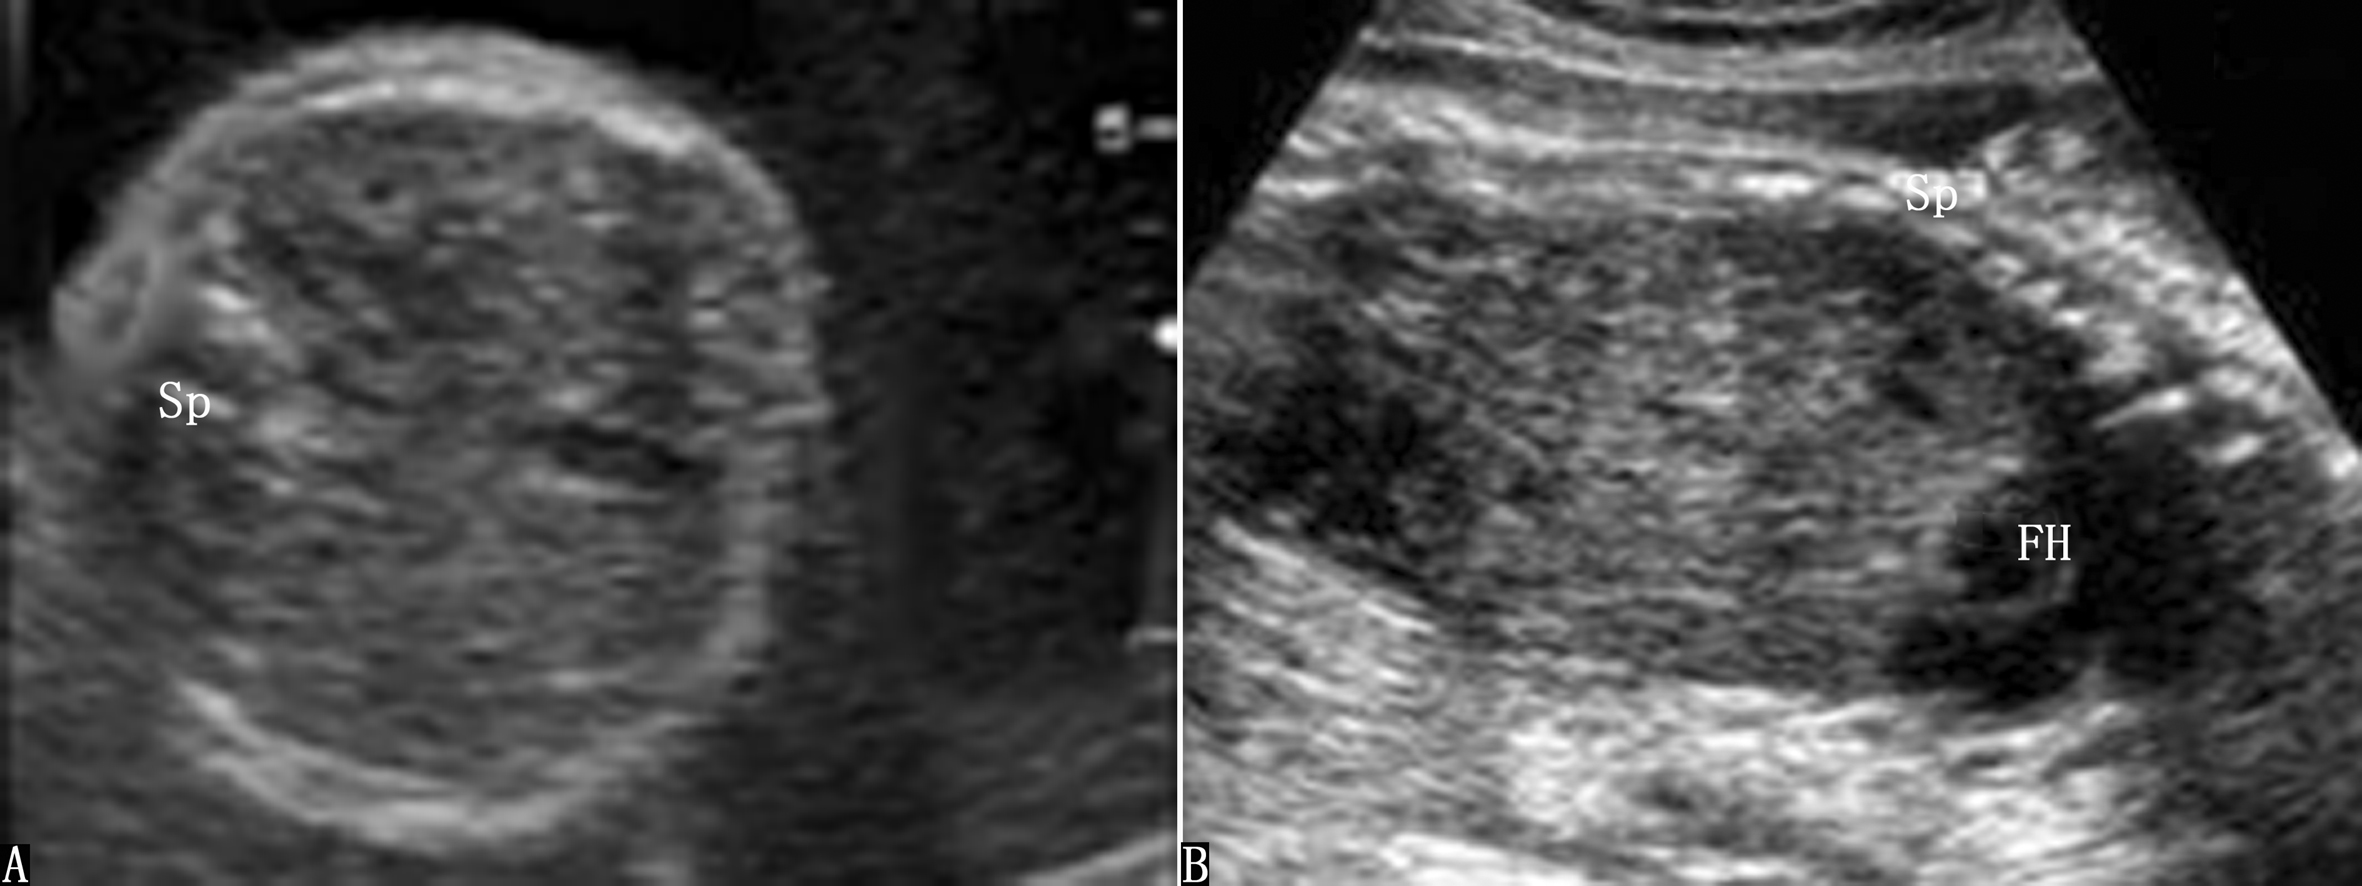

(1)胃泡不显示或小胃泡:超声在妊娠早期即可探查到胎儿胃泡,正常情况下孕14周以后胃泡显示率达100%。食道闭锁常导致胎儿胃泡无法显示,但由于气管食管瘘的存在和胃泡自身分泌作用,可出现小胃泡或胃泡大小正常。胃泡不显示并不仅仅提示单纯食道闭锁,合并气管食管瘘时亦可有此超声表现,食道闭锁声像图表现复杂多样,但对其分型相对困难。胎儿颜面部异常和胃泡位置异常也可引起胃泡不显示或小胃泡,由于食道闭锁与以上异常鉴别诊断并不困难,而且产前超声对于胃泡大小、形态可明确分辨,操作简单不易受胎儿体位干扰,早期即可进行观察(图2)。因此,观察胎儿胃泡形态学改变是诊断胎儿食道闭锁的要点之一。

图2食道闭锁声像图(孕15周):胎儿腹部胃泡不显示